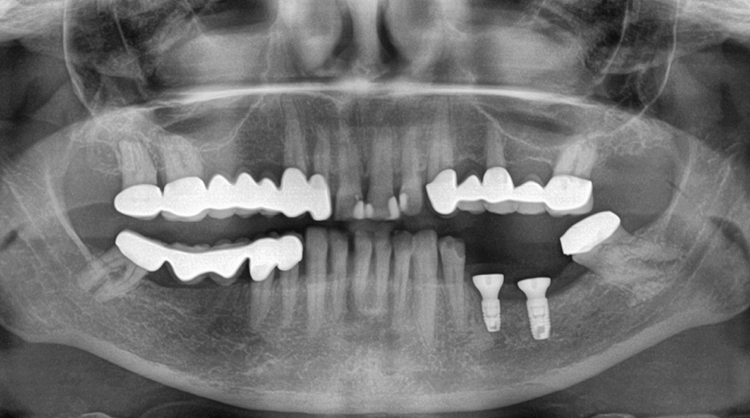

Es zeigte sich eine komplette Verknöcherung des Augmentats und keine Resorptionen im Bereich der Fixationsschrauben (Abb. 12) und es erfolgt die Entfernung der Osteosyntheseschrauben und die Implantation von zwei Implantaten (Abb. 13 und 14). Nun erfolgt das Vernähen des Mukosalappens apikal am Periost im Rahmen der Kazanjian Vestibulumplastik, um das Vestibulum wieder zu rekonstruieren (Abb. 15). Die offene Wundfläche Richtung Wange wird der sekundären Wundgranulation überlassen.

Die Verschraubung stellt eine wichtige Prävention gegen das Auftreten einer Periimplantitis dar. Das röntgenologische Abschlussfoto zeigt die knöcherne Regeneration des Defektes und gute Osseointegration der Implantate (Abb. 21).